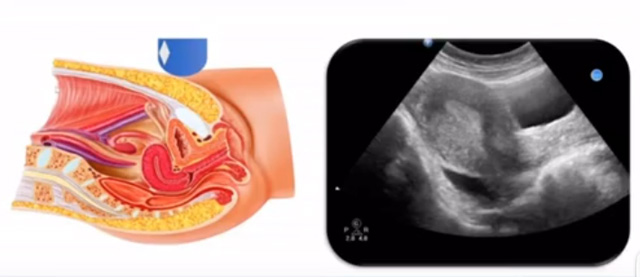

女性生殖系统包括内、外生殖器官及其相关组织以及邻近器官,其中内生殖器是91抖音视频在线观看超声检查的主要对象。那么内生殖器包括阴道、子宫还有输卵管及卵巢。输卵管及卵巢称为子宫附件。子宫是倒置梨形,但是它是空腔厚壁肌性器官。它的正常值在育龄妇女。超声探头放在贴近腹壁盆腔上面位置,来看这个子宫在超声上面的表现。从轮廓上来讲,和示意图是一样的。这就是在超声上面显示的一个子宫的图片。子宫在不同的时期与子宫颈的比例。成年妇女指的是育龄妇女为2:1子宫体是比较大的,婴儿期为1:2说明宫颈比较大,绝经期1:1。所以91抖音视频在线观看在看到子宫图时候可以根据宫体宫颈比例大致可以推测属于哪个时期的妇女。另外还可以根据比例大小来推断是一个正常子宫还是异常子宫。

子宫从外到内,浆膜层、肌层、粘膜层。宫体部宫颈为梭形结构。宫腔为上宽下窄的三角形,连接为峡部。子宫有什么功能呢?月经血产生跟排出通道,精子运行通道受精作用。囊胚着床及胎儿发育、生长的场所。分娩时产生宫缩使胎儿、胎盘娩出。未孕的子宫是很小的,已孕子宫就非常大,平均胎儿都有6斤重。所以这个后壁就体现出来。输卵管由子宫角部向外延伸,为一对细长而弯曲的管道,呈管状中空结构,大概长度是8-14厘米,粗1-4毫米,它的下方为卵巢和阔韧带。间质部是厚一点的,峡部是比较窄的地方,壶腹部,漏斗部。正常情况下,输卵管在普通超声DR难以显示。